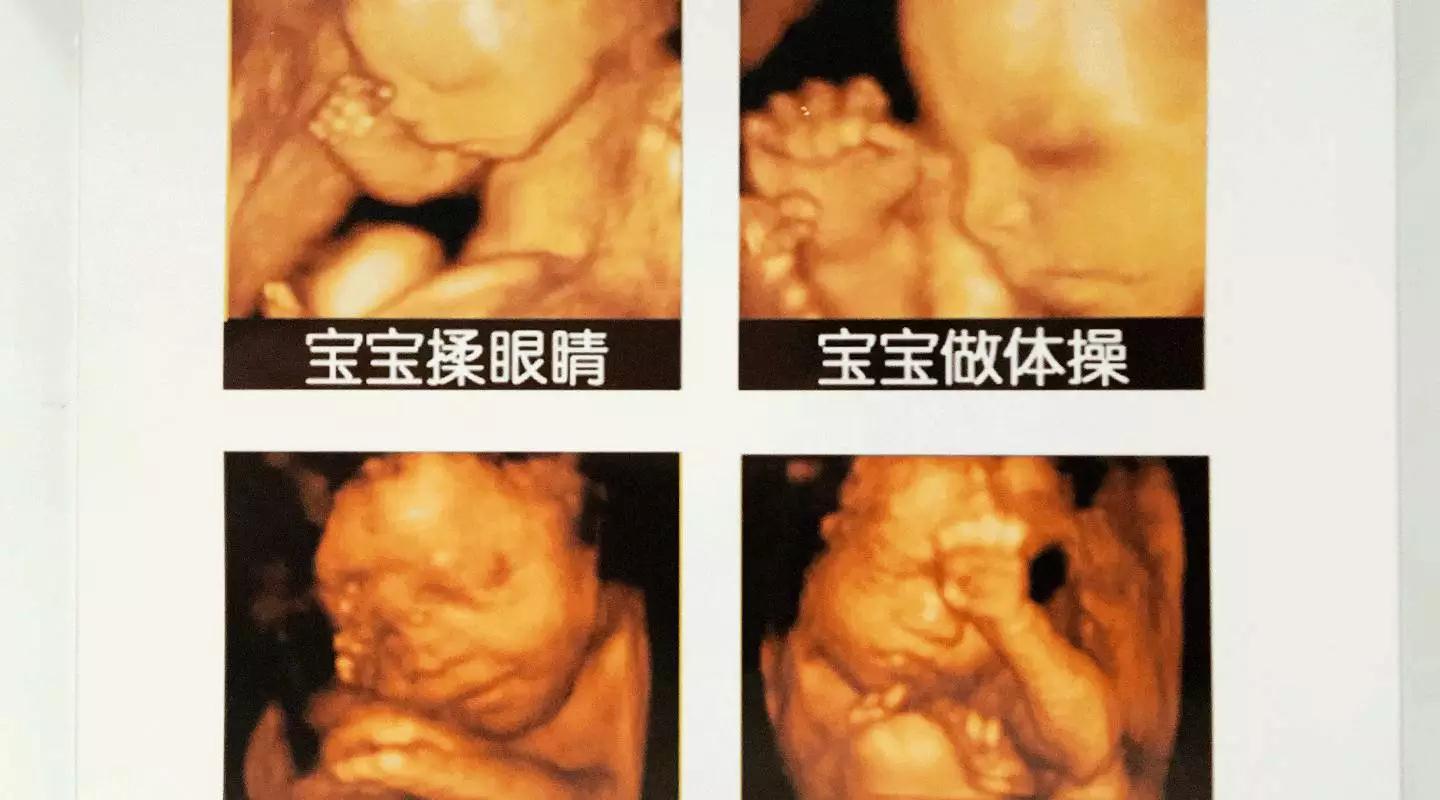

美GE不仅能提供包括腹部、血管、小器官、产科、妇科、泌尿科、新生儿和儿科等多领域的多方面的应用,而且能够显示未出生的宝宝的实时动态活动图像,为胎儿进行宫内拍“写真”和动态录像,让宝宝拥有完整的0岁相册。通过四维彩超(四维彩超),可以看到宫内胎儿打哈欠、伸懒腰、吮手指等萌萌的动作,让准爸妈们增添了安心和乐趣,不再仅仅是感觉宝宝的呼吸和运动,可以亲眼目睹宝宝的举动和乖巧容颜。还可以打印宫内高清写真,作为送给未来宝宝的珍贵礼物!

把握做四维彩超(四维彩超)的佳时间

四维彩超(四维彩超)检查的适宜时间是孕期22-26周。此时胎儿大小及羊水适中,活动度大,体表也比较丰满,利于胎儿超声成像和胎儿畸形筛查。孕妈们定要注意四维彩超(四维彩超)检查的佳时间,提前做好预约准备哦。(点阅读原文可咨询预约)

四维彩超(四维彩超)

宝宝的0岁照片